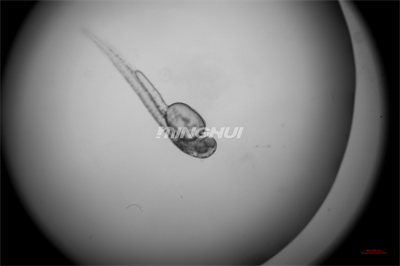

4倍半復(fù)消色差物鏡觀察的效果

1.半復(fù)消色差物鏡系統(tǒng):配備4×、10×、20×半復(fù)消色差物鏡,有效消除色差與球差,尤其在20倍率下仍能保持心臟邊緣成像銳利,清晰呈現(xiàn)心室收縮舒張過程中心肌細(xì)胞的運(yùn)動細(xì)節(jié)。